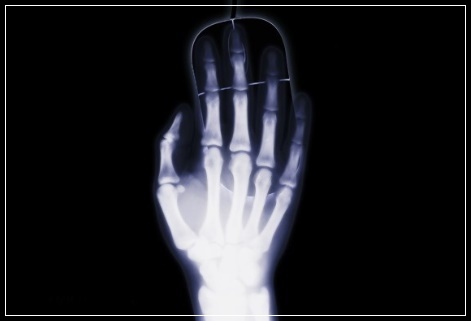

손목터널은 손목에서 손가락을 움직이는 힘줄과 정중신경이 통과하는 인대와 뼈로 이루어진 터널 같은 구조를 말하는데 이 터널이 좁아지거나 터널을 지나는 힘줄 등의 구조물이 두꺼워지면 터널 안을 지나는 정중신경이 압박을 받게 되어 엄지손가락부터 넷째 손가락까지 손가락 끝의 저림과 통증이 발생합니다.

손목터널증후군은 폐경기 이후 중년여성에게 흔하지만 젊은 여성이나 남성에서도 손을 많이 사용하는 직업을 가진 사람에게 주로 발병하는데 힘든 일이 아니더라도 손가락을 많이 움직이면 손목 터널 안에서 힘줄의 마찰이 일어나 염증이 생기고 이에 부기가 신경을 압박해서 손가락이 저리는 것입니다. 이렇게 손목 터널 내의 압력이 증가되면 이에 반응해서 터널을 만드는 인대도 더 두꺼워지게 되어 터널은 더 좁아지게 되어 점점 증상이 심해지게 됩니다.